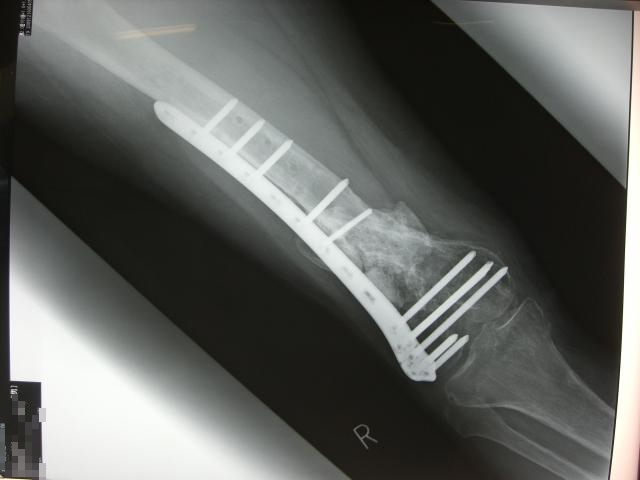

º£Ç¯½é¤á¤Æ¤Î¿Ç»¡¤Ø¹Ô¤Ã¤ÆÍè¤Þ¤·¤¿¡£¤â¤¦²¿»þ¤Ç¤âºÆ¼ê½Ñ¤¬½ÐÍè¤ë¾õÂÖ¤Þ¤Ç

¹ü¤¬½ÐÍè¾å¤¬¤Ã¤ÆÍè¤Æ¤¤¤Þ¤¹¡£

¤Ç¤â¡¢¿§¡¹¤ÈÅԹ礬¤¢¤ë¤Î¤Ç

Dr¤Ë¤Ï¤â¤¦¾¯¤·Àè¤Ë¡¦¡¦¡¦¤Èµ¤»ý¤ÁŪ¤Ë¤Ï¡¢Çß±«Á°¤ËÆþ±¡

Çß±«¤¬½ª¤Ã¤ÆÂౡ¤·¤Æ¥Ð¥¤¥¯¤Ë¾è¤ê¤Þ¤¯¤ë

¤È¸À¤¦¤Î¤¬°ìÈÖÍýÁۤǤ¹¤¬¡¦¡¦¡¦

¹ü±äŤò¤ä¤ë¤ÈȾǯ¤Ïư¤±¤Ê¤¤¤·¡¢É¨¤ò¶Ê¤²¤ë¤È¥Ð¥¤¥¯¤Ë¾è¤ì¤Ê¤¤¤·¡¦¡¦¡¦

¼è¹ç¤¨¤º¥×¥ì¡¼¥È¤Ïº£Ç¯Ãæ¤Ë¼è¤é¤Ê¤¤¤È¤¤¤±¤Ê¤¤¤Î¤Ç

¥Ð¥ê¥å¡¼¥»¥Ã¥È¤Ç¤ª´ê¤¤¤·¤è¤¦¤«¤Ê¡£